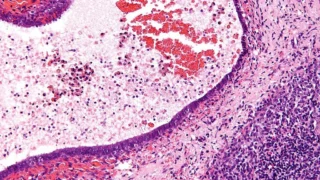

Does Surgery Reduce Iron Deposition in Ovarian Endometriomas? - RBMO